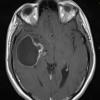

NEOPLASMS (GLIAL)

Glioblastoma, granular cell type (5)